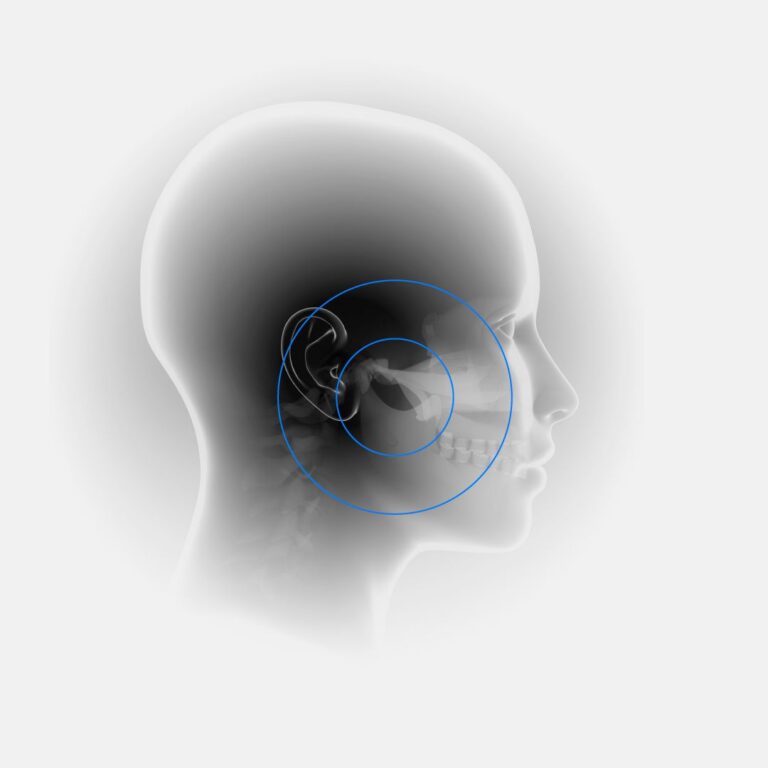

Η κροταφογναθική διάρθρωση (ΚΓΔ) αποτελεί μια σύνθετη άρθρωση που συνδέει την κάτω γνάθο με το κροταφικό οστό του κρανίου. Βρίσκεται μπροστά από το αυτί και επιτρέπει τη φυσιολογική κίνηση της κάτω γνάθου, όπως το άνοιγμα και κλείσιμο του στόματος, την πλευρική κίνηση και την προώθηση της γνάθου προς τα εμπρός.

Πρόκειται για μια από τις πιο περίπλοκες αρθρώσεις του ανθρώπινου σώματος, με την κίνηση να διευκολύνεται από την παρουσία ενός αρθρικού δίσκου.